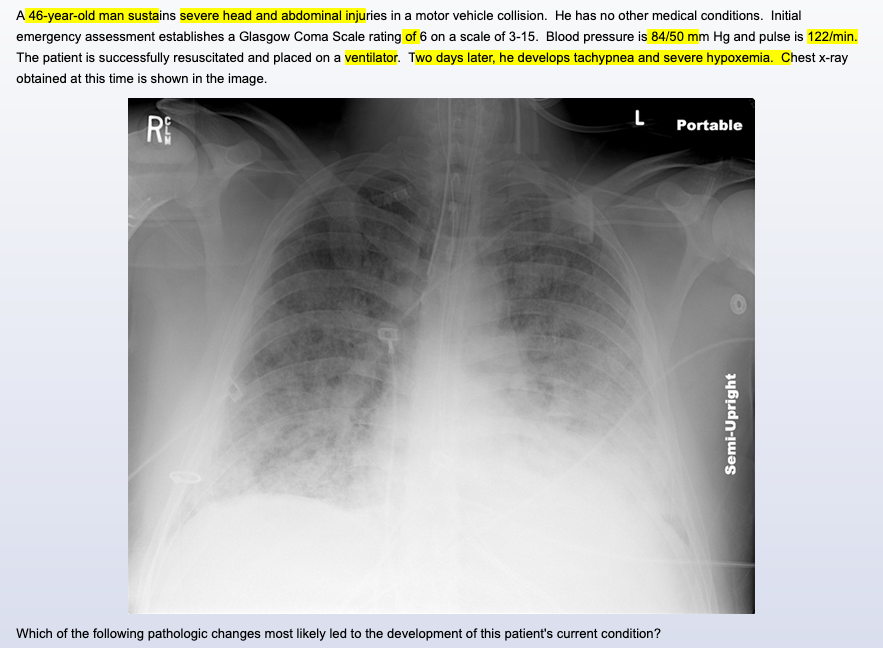

most likely dx